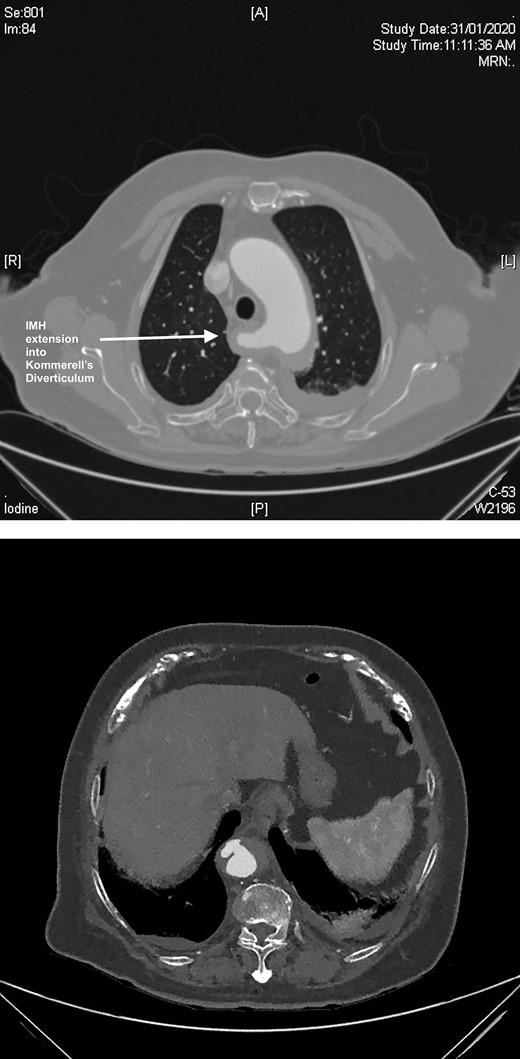

A computed tomography (CT) angiography was performed identifying a penetrating aortic ulcer (PAU) at the level of T11 with an intramural hematoma (IMH) extending to the inferior origin of the left subclavian artery origin (Fig. 1A). The IMH extended into ARSA with an associated KD (Fig. 1B). She was transferred immediately to the intensive care unit for anti-impulse therapy (dP/dt). The patient’s pain initially settled but then recurred during the admission and was refractory to blood pressure control.

(A) CT axial slice demonstrating PAU. (B) CT axial slice IMH seen extending into the KD.